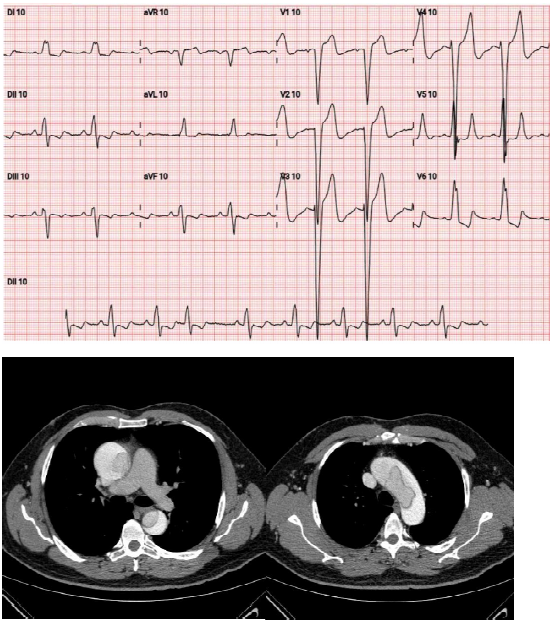

Sr. Manoel, 65 anos, procura pronto-socorro e relata forte dor retroesternal há 50 minutos e histórico de hipertensão

arterial. Ao exame clínico, as auscultas pulmonar e cardíaca estão normais, pressão arterial de 170x 100 mmHg,

frequência cardíaca de 76 bpm, frequência respiratória de 19 irpm, temperatura de 36,4º C e saturação de 97%.

Foram também realizados os exames abaixo:

Qual a conduta a ser adotada para esse caso?